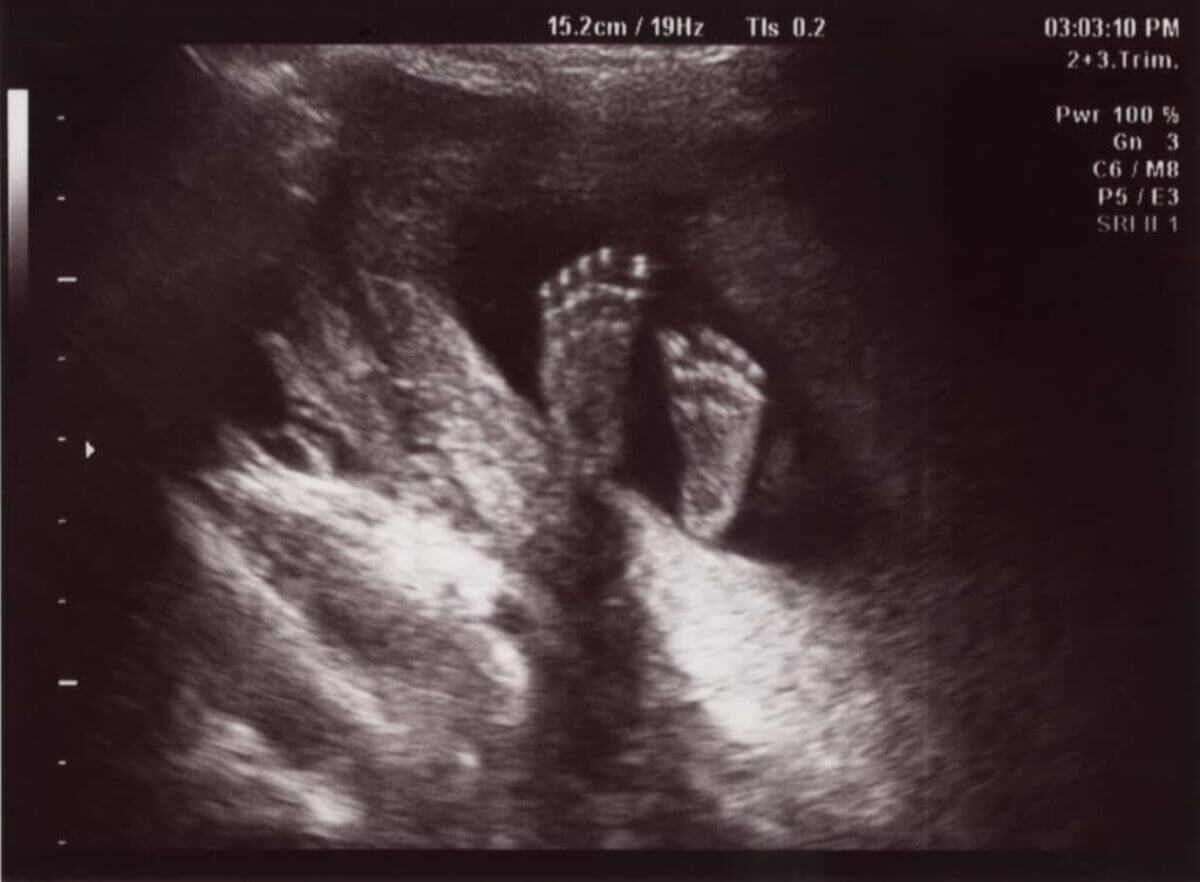

ज्या महिलांना गर्भधारणा करण्यात अडचण येत आहे त्यांच्या मूल्यांकन आणि व्यवस्थापनात वंध्यत्व अल्ट्रासाऊंड मोठी भूमिका बजावते. रुग्णांनी त्यांच्या काळजीने पुढे जात असताना अल्ट्रासाऊंड समजून घेणे महत्वाचे आहे.

अल्ट्रासाऊंडसह, "प्रोब" (ज्याला ट्रान्सड्यूसर असेही म्हणतात) द्वारे उच्च वारंवारता ध्वनी लाटा उत्सर्जित होतात. ध्वनी लहरी शरीरातील अवयव आणि ऊतींमधून उडी मारतात आणि परावर्तित ध्वनी लहरी प्रोबद्वारे प्राप्त होतात आणि मॉनिटरवरील प्रतिमांमध्ये लहरींची पुनर्रचना करण्यासाठी संगणकाचा वापर केला जातो.

बहुतेक अल्ट्रासाऊंड सपाट (किंवा द्विमितीय) प्रतिमा तयार करतात. काही मातृ आणि गर्भाचे औषध प्रदाता 3D किंवा 4D अल्ट्रासाऊंड देतात. 3 डी आणि 4 डी दोन्ही अल्ट्रासाऊंड गर्भाच्या आत आपल्या बाळाचे अधिक आजीवन दिसणारे दृश्य प्रदान करतात. 4 डी अल्ट्रासाऊंड थेट गती प्रदान करते. हे आपल्या बाळाच्या रिअल-टाइम हालचाली दर्शवते (चित्रपट पाहण्यासारखे).